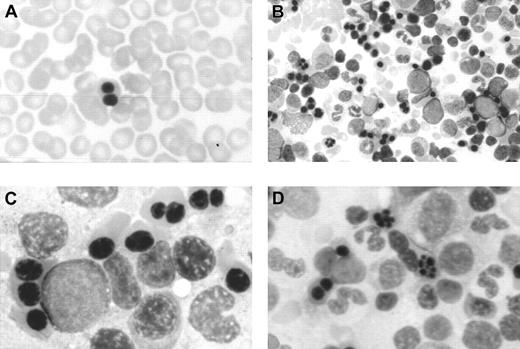

In this period, an extensive study ruled out red cell enzyme, membrane, hemoglobin, and thalassemic diseases. Tests for maternofetal isoimmunization were normal, and a bone marrow biopsy showed a normal osteogenesis with erythroid hyperplasia, excluding an aplastic red cell anemia. His red cells showed a normal agglutinability with anti-i antibody, and an acidified serum lysis test was negative (HEMPAS negative) in 3 samples and against 25 sera. At 3 months of life when the immunohematologic study was carried out, his hemoglobin was 67 g/L, mean corpuscular volume was 80 fL, platelets were 568 × 109/L, leucocytes were 10.2 × 109/L, including 10% of nucleated red cells, and reticulocytes were 0.5% (0.013 × 1012/L). Red cell morphology in peripheral blood showed scant binuclear erythroblasts (2%) (Figure 1).

Optical microscopy morphology of peripheral and bone marrow hematopoiesis.

Binucleate erythroblast in peripheral blood (A). Erythroid hyperplasia with marked abnormalities (binucleate, trinucleate, and multinucleate late erythroblasts) (B,C,D). Abnormal erythroblasts showing anomalous distribution of chromatin (C,D), binucleate erythroblasts, and isolated trinuclear, tetranuclear (B), and aberrant multinuclear erythroblasts (B,D). May-Grünwald-Giemsa stain. Original magnifications: A and D, × 400; B, × 200; C, × 1000.

Optical microscopy morphology of peripheral and bone marrow hematopoiesis.

Binucleate erythroblast in peripheral blood (A). Erythroid hyperplasia with marked abnormalities (binucleate, trinucleate, and multinucleate late erythroblasts) (B,C,D). Abnormal erythroblasts showing anomalous distribution of chromatin (C,D), binucleate erythroblasts, and isolated trinuclear, tetranuclear (B), and aberrant multinuclear erythroblasts (B,D). May-Grünwald-Giemsa stain. Original magnifications: A and D, × 400; B, × 200; C, × 1000.

At the age of 2 months a bone marrow examination showed erythroid hyperplasia and markedly abnormal erythropoiesis (Figure 1), including a substantial proportion of binuclear erythroblasts (20%) and a much smaller proportion of trinuclear, tetranuclear, and multinuclear erythroblasts (2%). Sideroblastic or megaloblastic anemias were ruled out. Granulocytopoiesis and megakariocytopoiesis were normal.